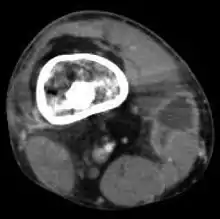

Mycobacterium doricum osteomyelitis and soft tissue infection. Computed tomography scan of the right lower extremity of a 21-year-old patient, showing abscess formation adjacent to nonunion of a right femur fracture.